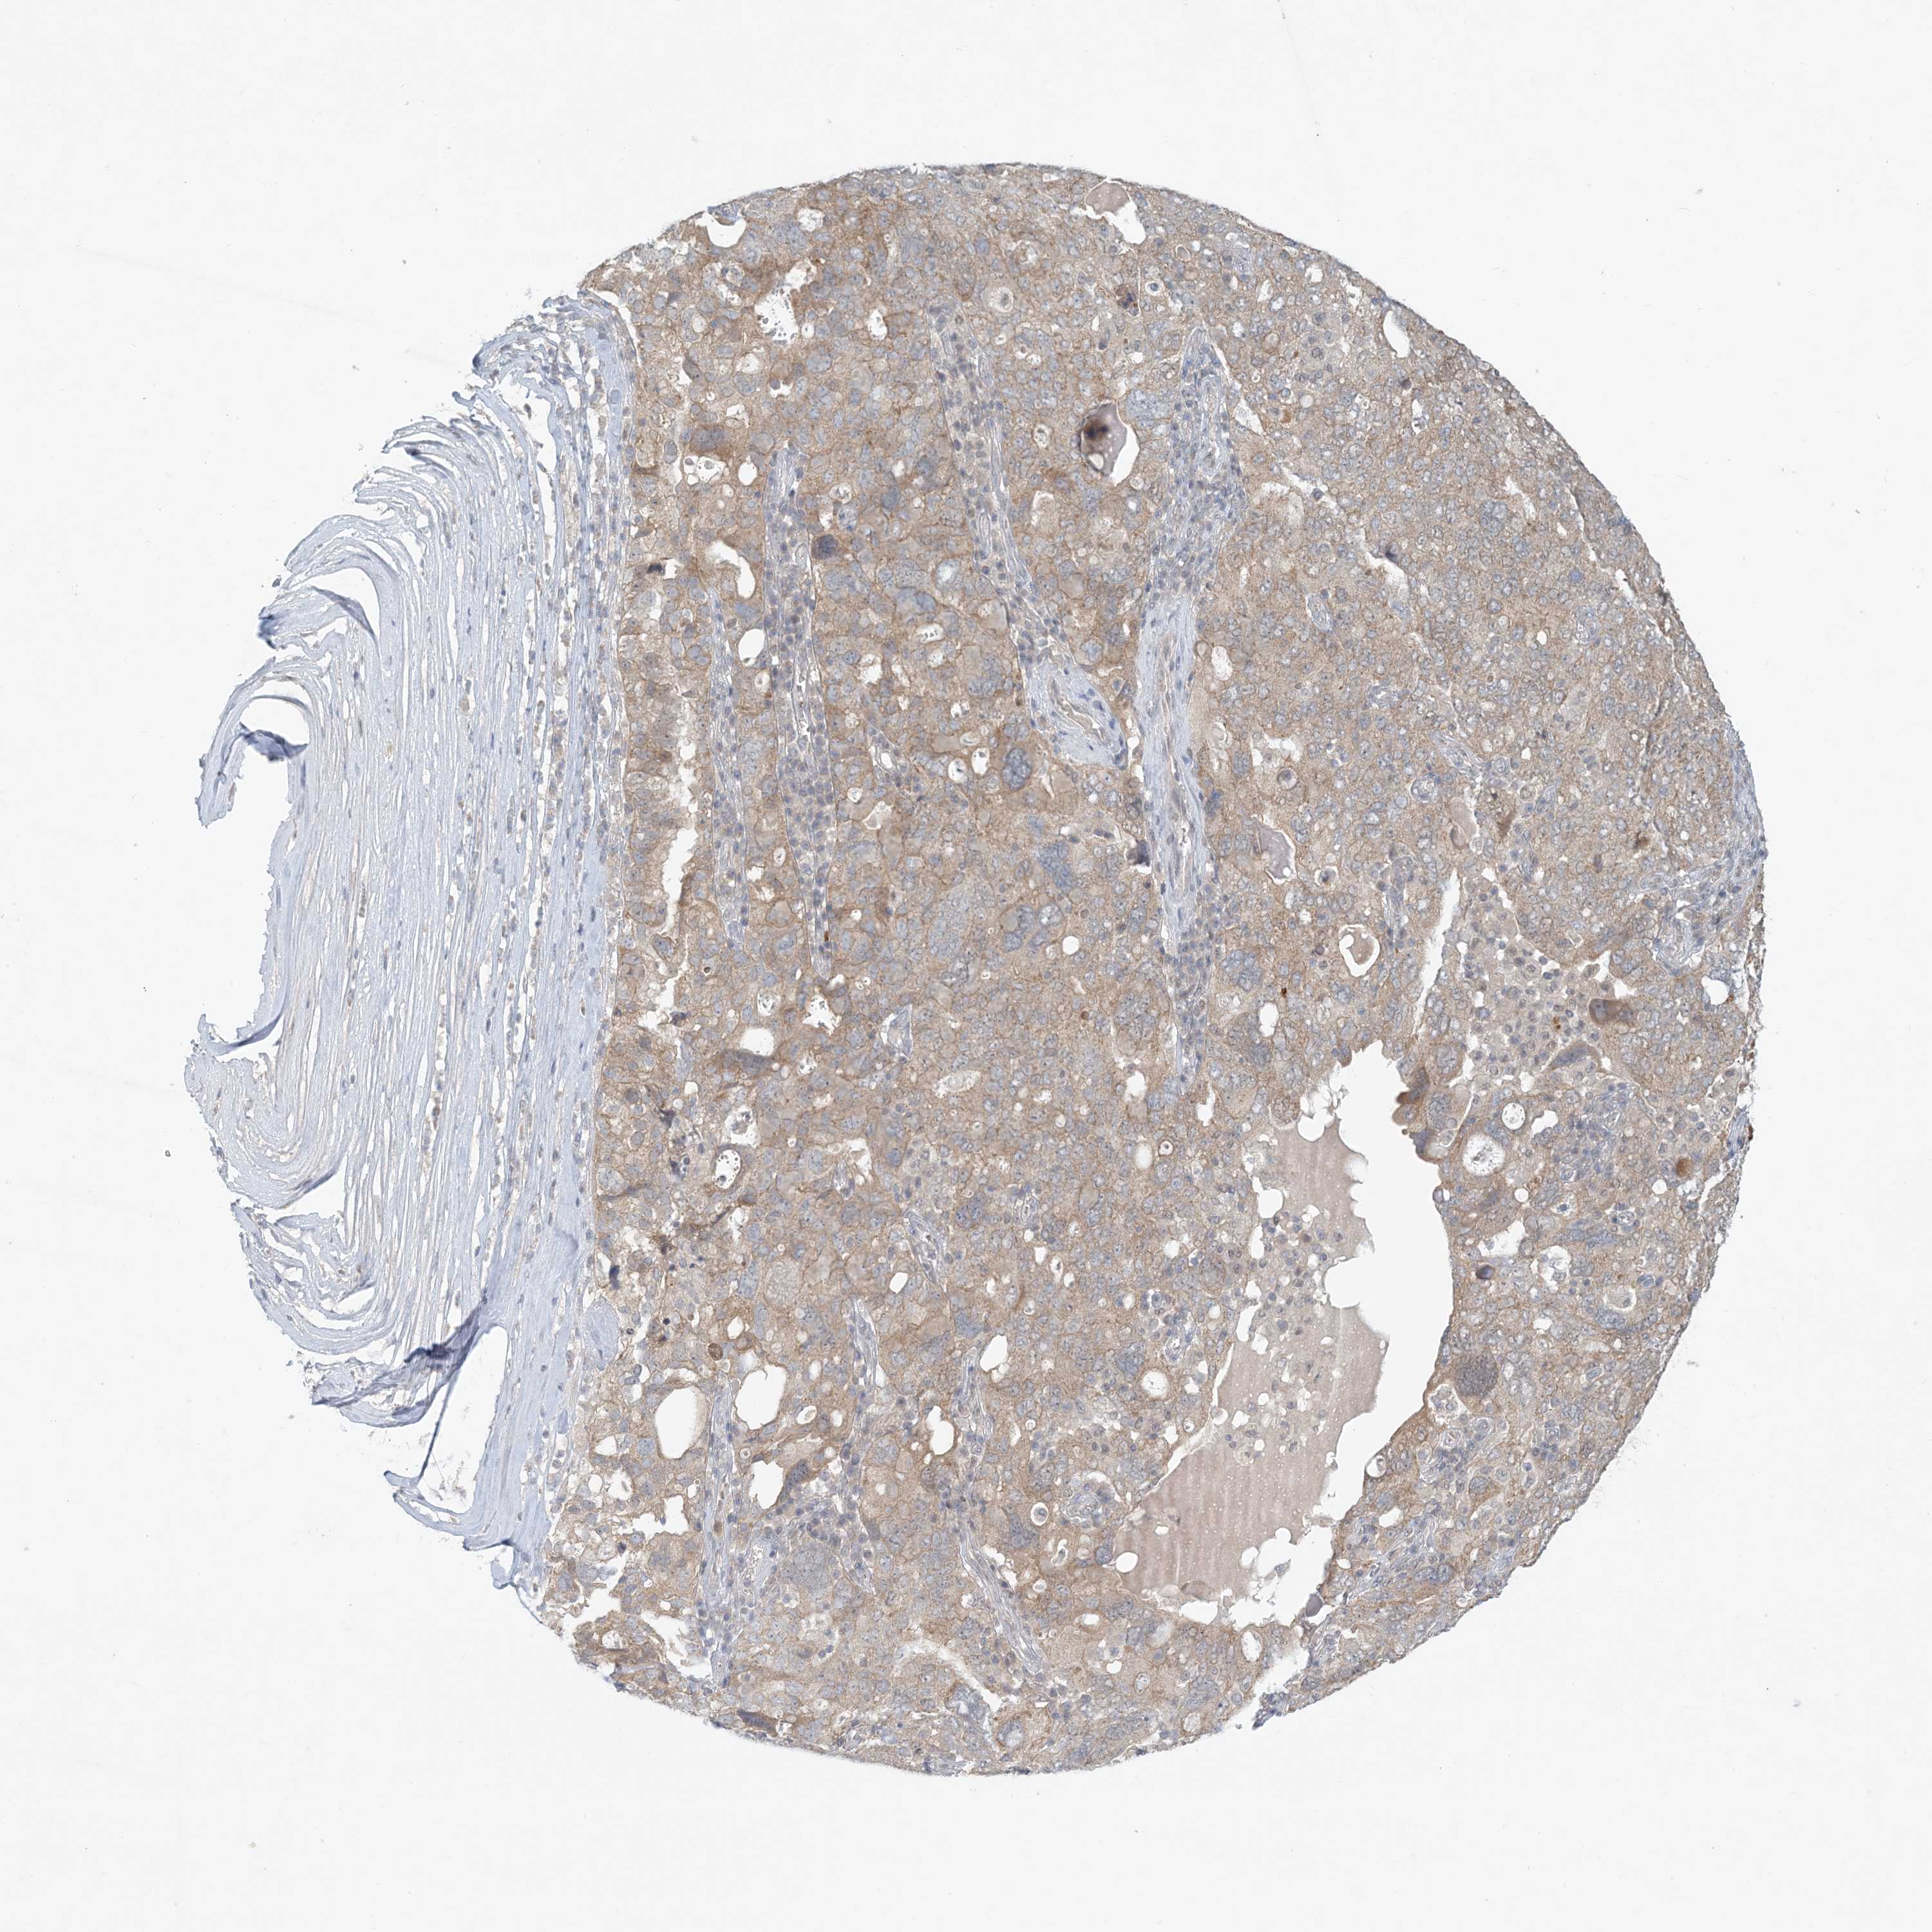

OVARIAN CANCER - Protein expressioni

A mouse-over function shows sample information and annotation data. Click on an image to view it in a full screen mode. Samples can be filtered based on level of antibody staining by selecting one or several of the following categories: high, medium, low and not detected. The assay and annotation is described here.

Note that samples used for immunohistochemistry by the Human Protein Atlas do not correspond to samples in the TCGA dataset.

Antibody stainingi

Antibody staining in the annotated cell types in the current human tissue is reported as not detected, low, medium, or high, based on conventional immunohistochemistry profiling in selected tissues. This score is based on the combination of the staining intensity and fraction of stained cells.

Each image is clickable and will lead to virtual microscopy that enables deeper exploration of all samples and also displays staining intensity scores, fraction scores and subcellular localization as well as patient and tissue information for each sample.

Antibody HPA034785

Antibody HPA034786

Cystadenocarcinoma, serous, NOS

Carcinoma, endometroid

Cystadenocarcinoma, mucinous, NOS

Carcinoma, NOS